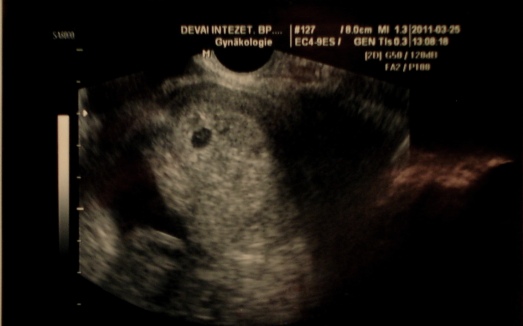

még magam is nehezen hiszem el...de olyankor megnézem a kis képecskét amit kaptam. :D :D :D

megmutatom nektek is. kb középen kell nézni a nagyobb fekete foltot és közvetlen mellette jobb oldalt a kicsikét.

Kép

Parane, tündéri a kismanó!!!!! A másik babó tényleg nagyon picike, de ami tuti, hogy a nagy fekete folt szép, erős, egészséges :)

"Csíp-csíp", megcsíplek, hidd el, nem álmodsz, már hárman vagytok Apával :)